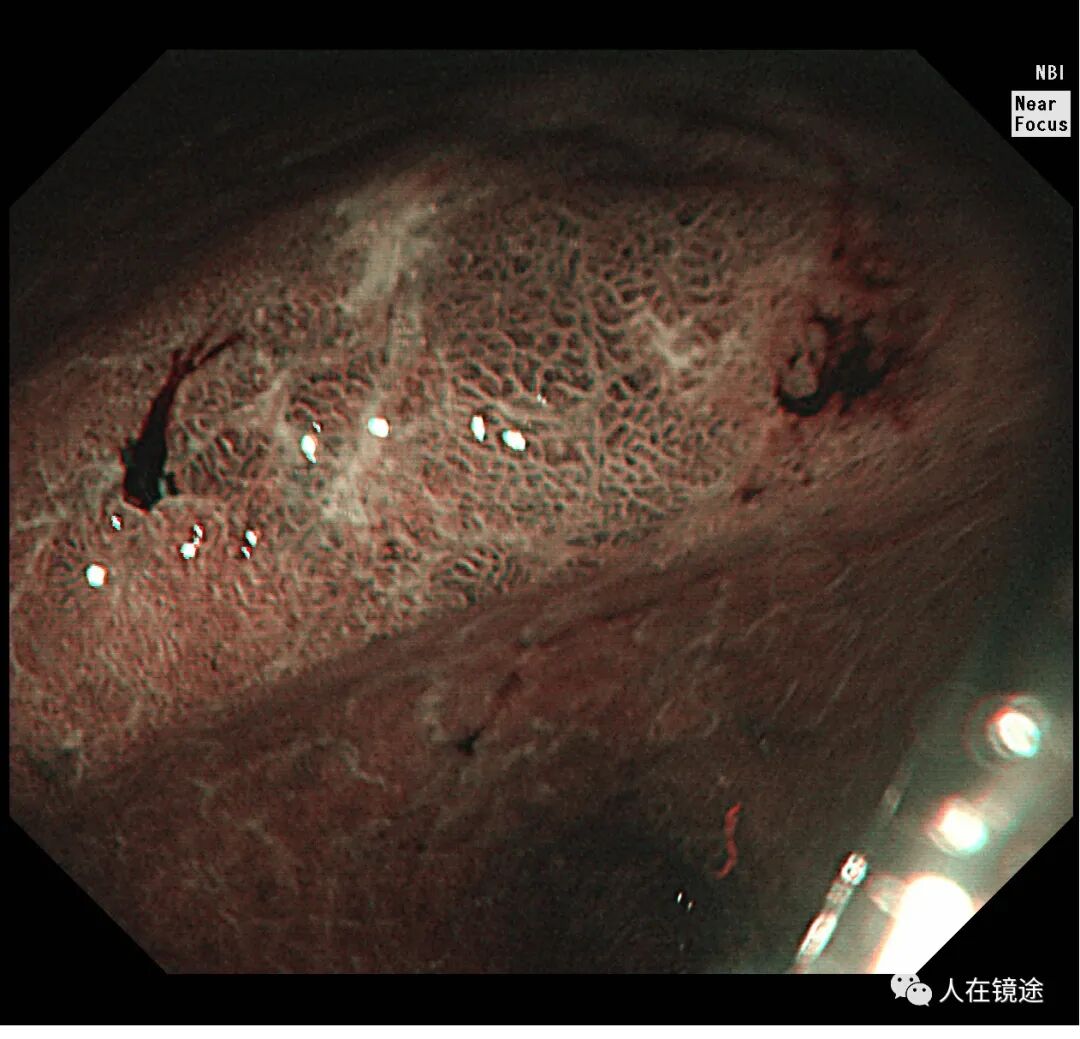

NBI示:胃窦小弯见一0.8*1.2cmIIa粘膜病变呈咖色,边界清楚,表面粘膜高低不平伴自发性出血。

NBI+近焦示:胃窦小弯见一0.8*1.2cmIIa粘膜发病变呈咖色,边界清楚,微结构紊乱,表面粘膜高低不平伴自发性出血